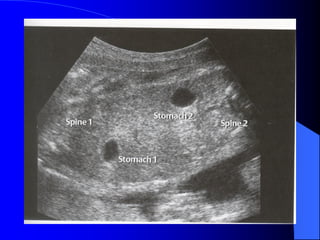

I. Ñònh nghóa: Hoäichöùng naøy chæ coù ôû song thai dò hôïp tö. Do söï maát caân baèng thoâng noái ñoäng tónh maïch trong baùnh nhau daãn ñeán söï toån thöông maïch maùu ôû thai. Thai cho cung caáp maùu cho thai nhaän cho neân thai cho chaäm taêng tröôõng vaø thai nhaän bò phuø. Thai nhaän coù theå bò suy tim. Hai thai coù theå cheát trong töû cung. Ña oái chieám tæ leä raát cao.

II. Taàn xuaát: -Khoaûng 5-10% trong caùc loaïi song thai - Khoaûng 5% song thai dò hôïp töû. III. Caùc hoäi chöùng keát hôïp: - Thai cho: thieáu maùu, chaäm taêng tröôûng, thieåu oái, voâ oái. - Thai nhaän : thai lôùn, ña oái, suy tim, phuø thai

IV. Daáu hieäutreân sieâu aâm:  Song thai dò hôïp töû thöôøng thaáy hai tuùi oái.  Söï maát caân ñoái veà taêng tröôûng giöõa hai thai.  Thöôøng cuøng giôùi tính.  Thai nhaän to, suy tim, phuø thai vaø ña oái.  Thai cho thöôøng thaáy thieåu oái hay voâ oái.  Chu vi cuûa ñoäng maïch roán khoâng hôïp lí.  Van nhó thaát cuûa thai nhaän bò giaûm khaû naêng do ña oái quaù taûi tuaàn hoaøn.  Hieám coù söï traùo ñoåi tuaàn hoaøn cuûa hai thai.